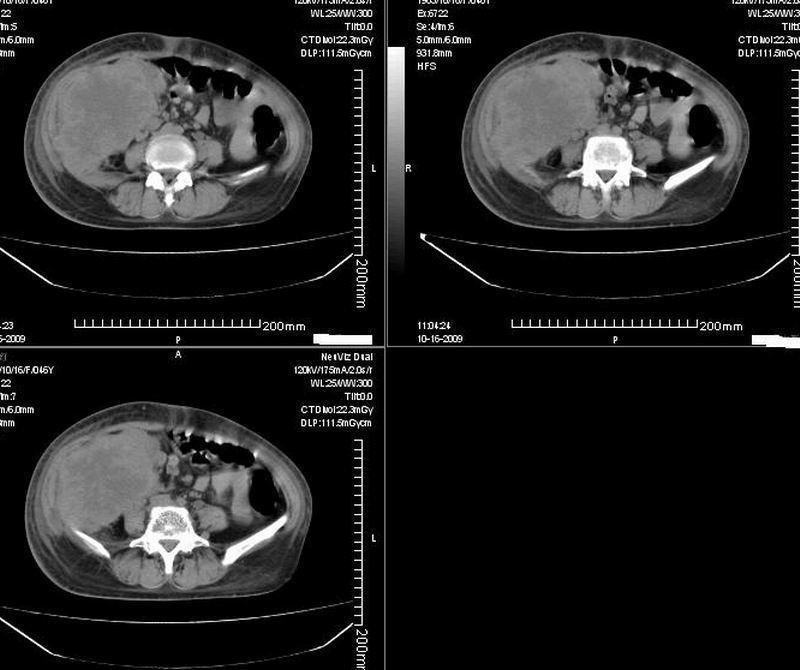

女:46y:一年前宫颈癌术后,现右下腹抚及肿块。

考虑宫颈癌术后复发周边侵犯/右中下腹及双侧腹股沟淋巴结转移。